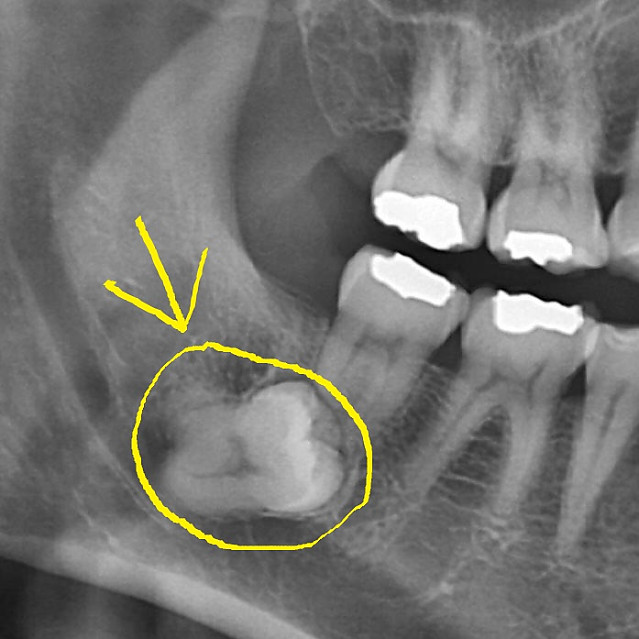

치과의사도 기도하게 만드는 X-레이 짤 작성자 정보 붐붐의민족 작성 작성일 2025.04.19 16:49 컨텐츠 정보 16,124 조회 목록 본문 이 정도면 사랑니 발치 고난도라고 합니다. 문외한인 제가 봐도 왠지 움찔하게 되네요...;; 관련자료 링크 https://www.kaov.org/KA_3101/%EC%B9%98%EA%B3%BC%EC%9D%98%EC%82%AC%EB%8F%84-%EA%B8%B0%EB%8F%84%ED%95%98%EA%B2%8C-%EB%A7%8C%EB%93%9C%EB%8A%94-x-%EB%A0%88%EC%9D%B4-%EC%A7%A4/ 732 회 연결 댓글 0 등록된 댓글이 없습니다. 로그인한 회원만 댓글 등록이 가능합니다. 목록